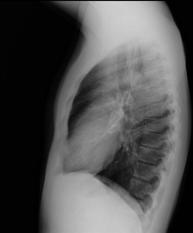

- Tòrax

- RX Tòrax

Tècnica que usa els raigs X a través de la qual s'obtenen imatges de la caixa toràcica (cor, pulmó, arcs costal, clavícules, etc.) per al seu estudi. - RX Ester

Una radiografia de tòrax és una tècnica mitjançant la qual, amb l'ús d'una petita dosi de radiació, s'obté una imatge bidimensional de la caixa toràcica i el seu contingut (pulmons, cor, mediastí, etc. ). És una de les proves mèdiques realitzades més comuna. - RX Abdomen